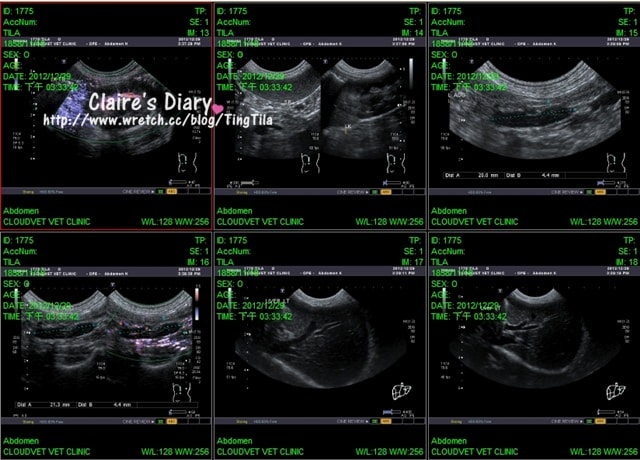

((超音波截圖一共30張!!))

(每張縮圖的右下角,都有正在照抄音波的部位只是))

在腎臟的部份,超音波照的比較久

這是因為TILA有多血症的關係,所以要觀看她血液的透析是否良好

如果黏稠就會通過的比較差,但整體看下來~都很順!還好^^

腎上腺也都正常4.4OK!!

所以TILA水的喝多尿多跟腎上腺機能亢進是沒有關係的!!

整體器官都很正常,就連很大的膽也長的非常漂亮!!